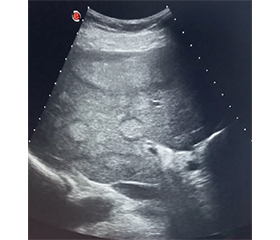

Гепатоцелюлярна карцинома (ГЦК) є найпоширенішим варіантом первинного раку печінки, що характеризується високою летальністю та несприятливим прогнозом. Глобальна захворюваність і смертність від ГЦК продовжують зростати попри прогрес у лікуванні вірусних гепатитів внаслідок зростання поширеності метаболічно-асоційованої стеатотичної хвороби печінки й ожиріння. На основі аналізу літературних джерел баз даних Pubmed, MedLine, The Cochrane Library, Embase в огляді узагальнено сучасні дані щодо епідеміології, ключових факторів ризику, патогенезу та молекулярної класифікації ГЦК. Окрему увагу приділено сучасним підходам до діагностики, зокрема методам візуалізації, системі стандартизації зображень LI-RADS, ролі неінвазивних біомаркерів і морфологічної верифікації. Підкреслено значення скринінгових програм у групах високого ризику та своєчасної міждисциплінарної взаємодії, що дозволяє оптимізувати стратегію ведення пацієнтів відповідно до міжнародних клінічних рекомендацій.

Hepatocellular carcinoma (HCC) is the most common variant of primary liver cancer, characterized by high mortality and unfavorable prognosis. Global incidence and mortality from HCC continue to rise despite progress in the treatment of viral hepatitis due to the increasing prevalence of metabolic dysfunction-associated steatotic liver disease and obesity. Based on the analysis of literature sources from the Pubmed, MedLine, The Cochrane Library, Embase databases, the review summarizes current data on the epidemiology, key risk factors, pathogenesis and molecular classification of HCC. Special attention is paid to modern approaches to diagnosis, in particular imaging methods, the Liver Imaging Reporting and Data System, the role of non-invasive biomarkers and morphological verification. The importance of screening programs in high-risk groups and timely interdisciplinary interaction is emphasized, which allows optimizing the strategy of patient management in accordance with international clinical guidelines.